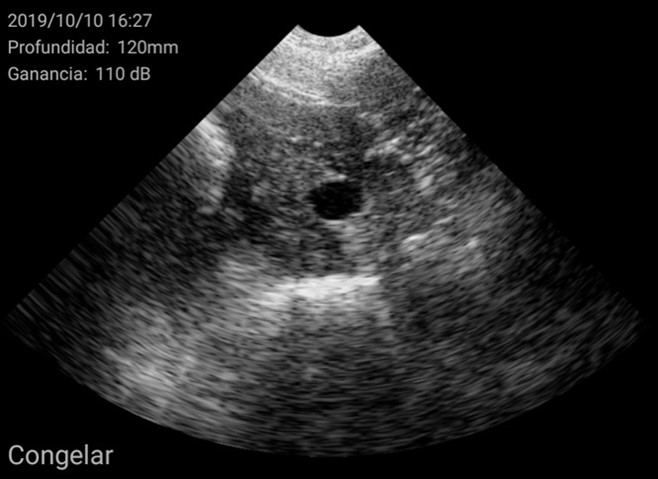

El diagnóstico se basó en la determinación del tamaño del útero y su posición en relación con otras estructuras como la vejiga urinaria o las asas intestinales. En general, se encuentra en posición ventral a la vejiga. Cuando el tamaño del útero es pequeño, ocupa muy poco espacio en la pantalla, de esta manera se considera una hembra impúber.

Imágenes de cerdas impúberes con el ecógrafo W3 de Kubus